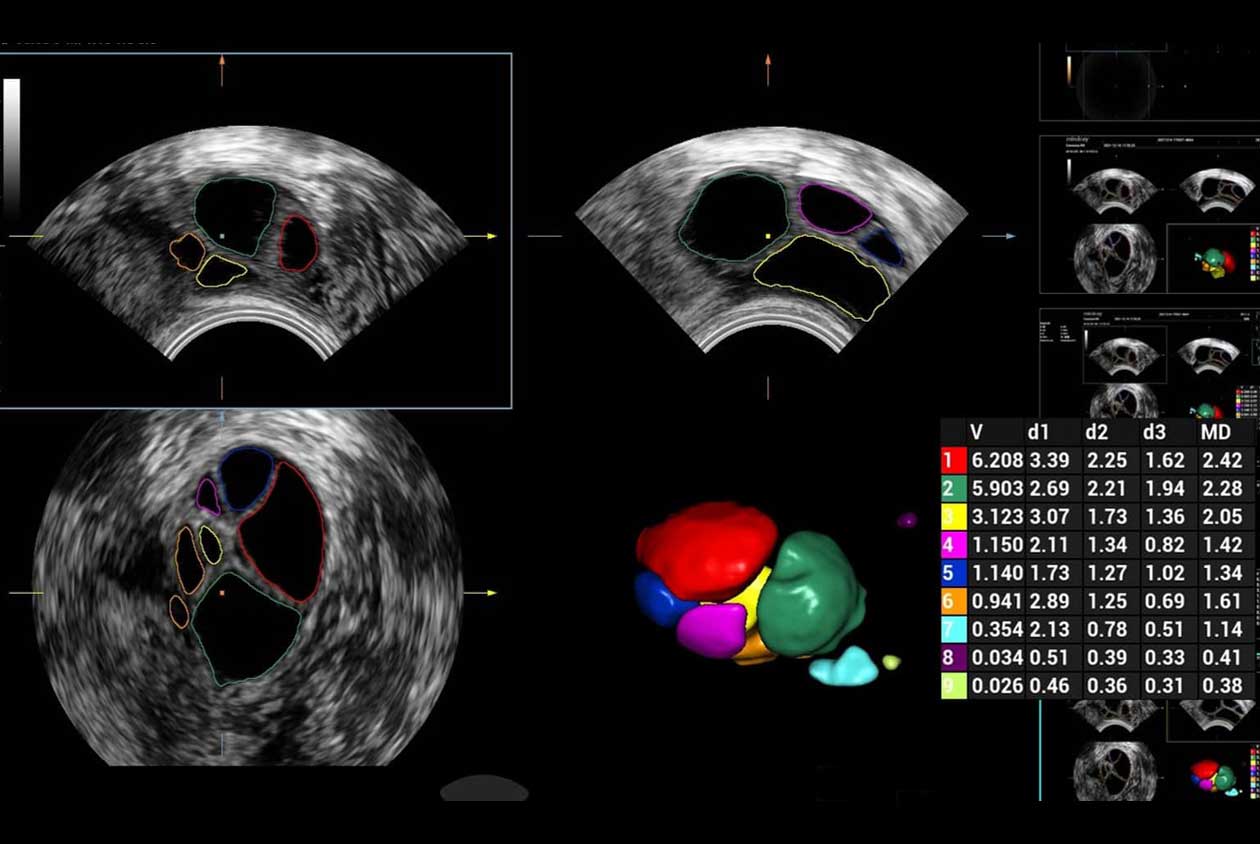

Women's Health | Radiology | Cardiovascular Imaging

Advanced Technologies

Enhancing Clinical Certainty

Clinical Images